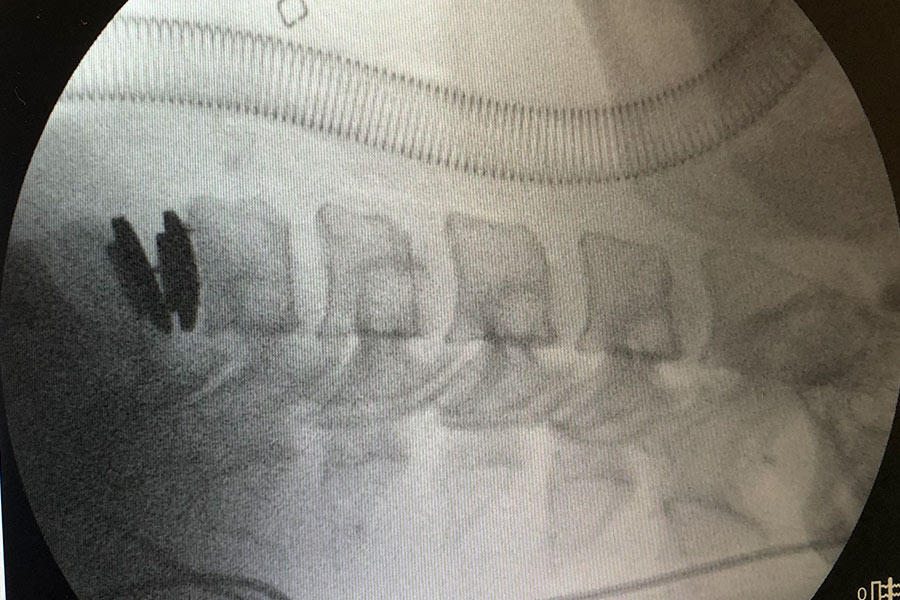

postcirugia-protesis-cervical-compleja

Postoperatorio

El paciente sale de quirófano con una movilidad completa del cuello y la única recomendación de no coger peso durante la primera fase de recuperación para evitar posibles lesiones en la zona.

Tras pasar la noche en el hospital, el paciente será dado de alta y tendrá que volver solamente para las futuras revisiones y consultas.